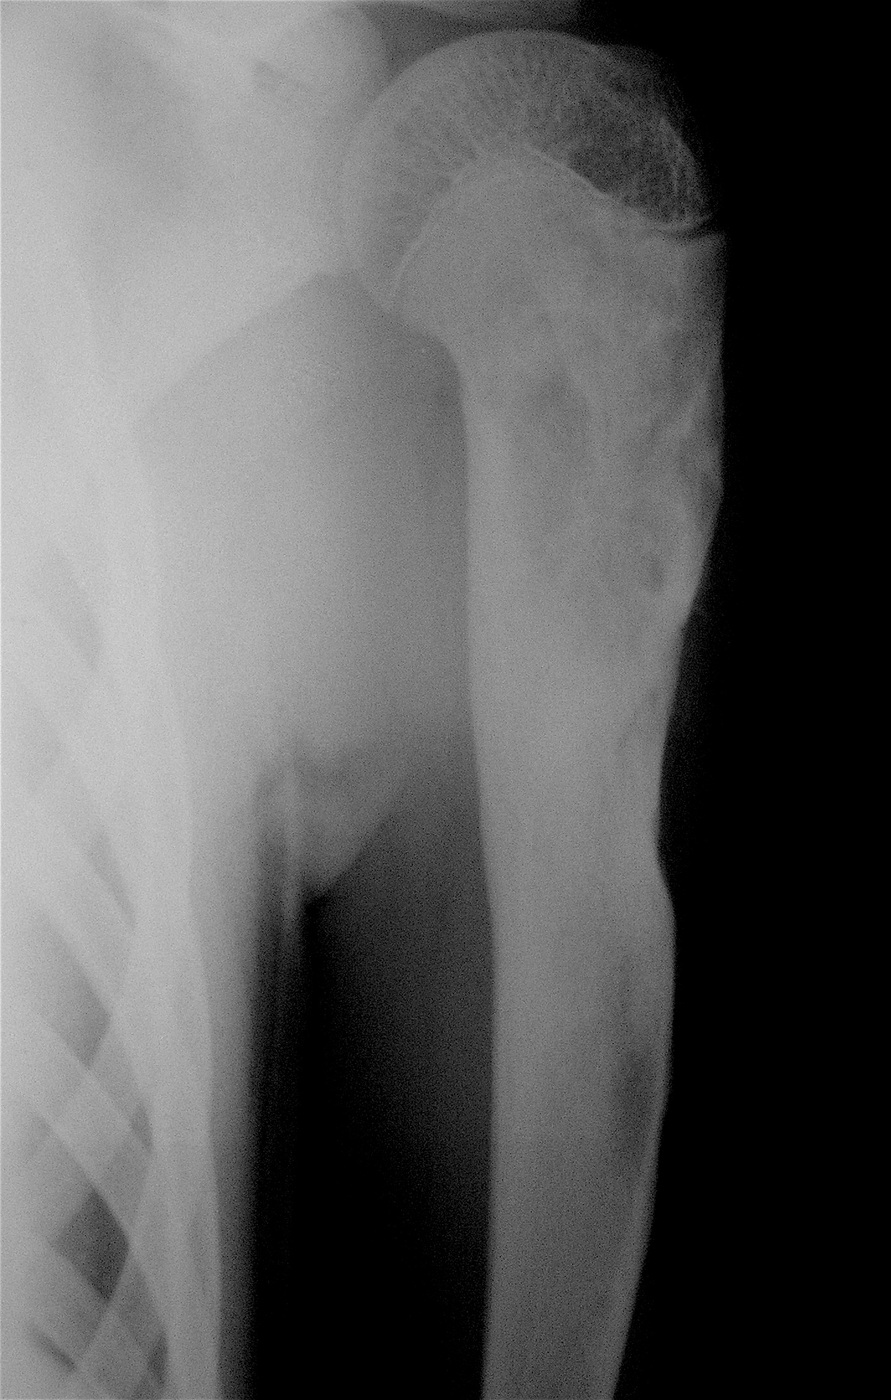

Аневризмальная киста проксимального метафиза левой плечевой кости.

Выполнена операция: экскохлеация кисты, аллопластика материалом «Лиопласт».